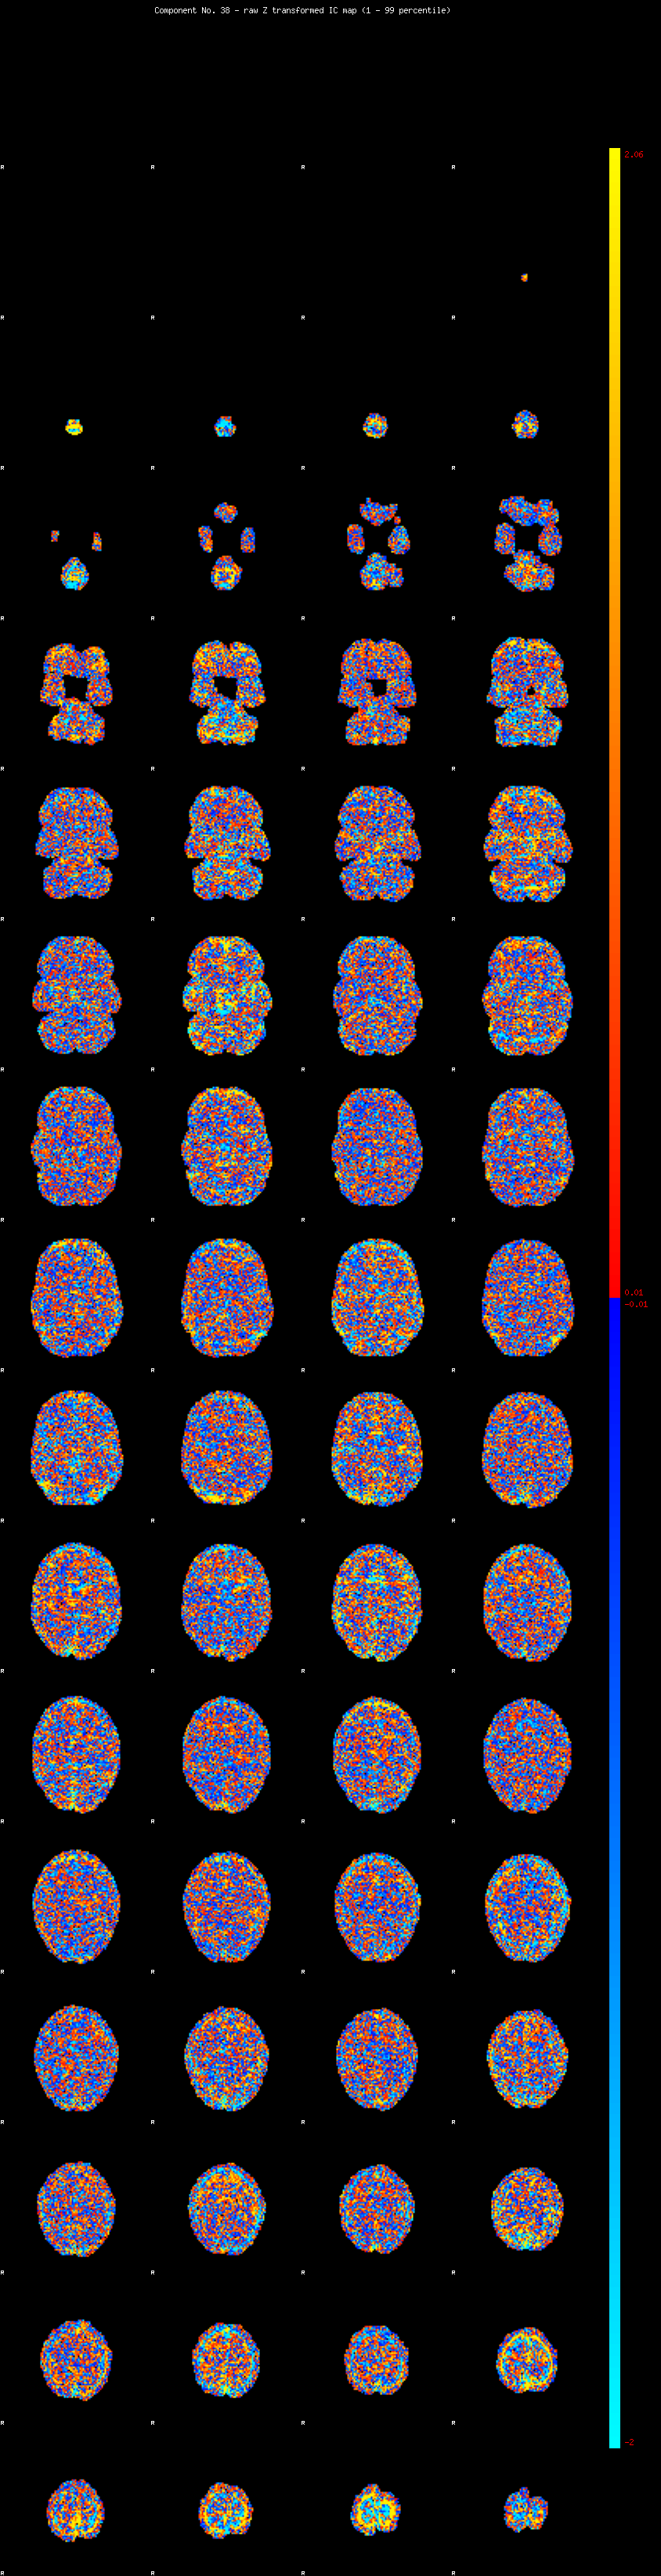

IC_38 Mixture Model fit

Means : 0.000000 2.388733 -2.248957

Vars : 1.000000 1.681692 1.288466

Prop. : 0.920503 0.041495 0.038002